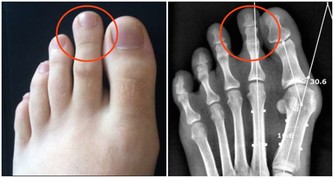

1、血液黏稠度在各種血型中,最容易升高。(健康隱患:腦梗塞)

3、末梢血管調節功能差,對冷刺激比較敏感。(健康隱患:凍瘡)